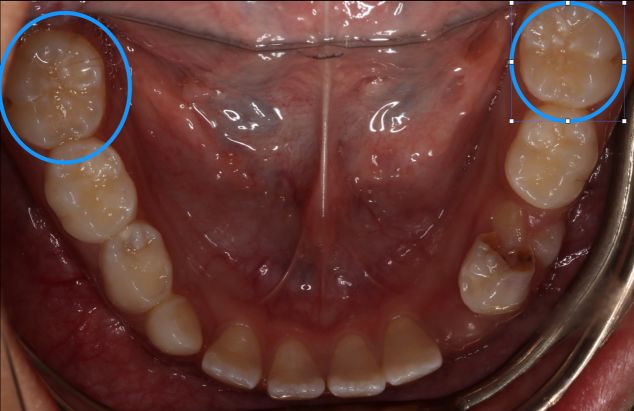

圆圈所示为第一恒磨牙(六龄齿)